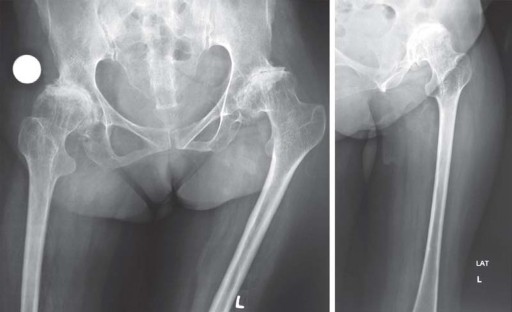

يشمل التقييم الإشعاعي للمريض تصوير العمود الفقري العنقي، وصورة شعاعية أمامية خلفية للحوض مع مفصلي الورك، وصورة جانبية لمفصل الورك المصاب، بالإضافة إلى صور أمامية خلفية وجانبية لعظم الفخذ. يساعد التخطيط المسبق للجراحة في اختيار الغرسة الصحيحة.

يميل مرضى التهاب المفاصل الروماتويدي اليفعي إلى امتلاك قناة نخاعية فخذية ضيقة جدًا مع عدم توافق بين قطر القناة القريبة والبعيدة. يمكن أن يختلف التجويف الحقي من النوع المشوه (كما يظهر في الشكل 29.1) إلى النوع المنغمس (كما يظهر في الشكل 29.2) أو قد يكون مفصل ورك ملتحم (كما يظهر في الشكل 29.3).

نمط الورك المشوه